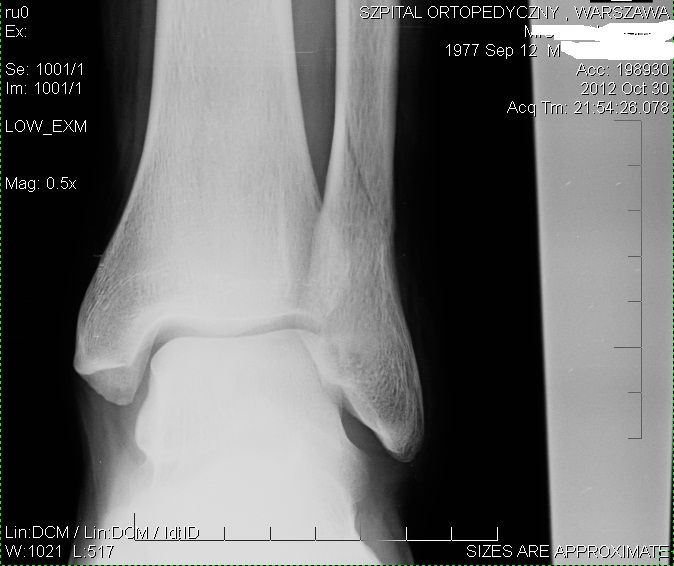

Dlaczego po trzech tygodniach od złamania strzałki i kości przyśrodkowej nie widać zrostu?

Po 3 tygodniach od zlamania strzalki i kostki przysrodowej, bez przemieszczen (bez zabiegu), nie widac zrostu. Wszystko wyglada jak w dniu zlamania. Lekarz mowi ze niby sie zrasta ale zdjecia porownalem i jest identycznie a nawet mam wrazenie ze gorzej,... Po 3 tygodniach od zlamania strzalki i kostki przysrodowej, bez przemieszczen (bez zabiegu), nie widac zrostu. Wszystko wyglada jak w dniu zlamania. Lekarz mowi ze niby sie zrasta ale zdjecia porownalem i jest identycznie a nawet mam wrazenie ze gorzej, ze akies przesuniecia. To normalne? Czy przypadkowe mocniejsze uderzenia gipsem syntetycznym w sciane podczas snu czy podczas wstawania z lozka moga przemiesic kosc? Kiedy efekty zrostu powinny byc widoczne? I kiedy moge zaczac stawac na nodze?

Złamanie kości strzałkowej bez przemieszczenia

Witam, 13 grudnia złamałem kość strzałkową prawej nogi. Złamanie podobno typowe, bez przemieszczenia dołączam link do zdjęcia RTG z rodzajem złamania http://i282.photobucket.com/albums/kk244/krynias_/zlamanie.jpg . Mam pytanie odnośnie usztywnienia nogi. Konkretnie założono mi gips do 2/3 uda i zastanawiam się czy do... Witam, 13 grudnia złamałem kość strzałkową prawej nogi. Złamanie podobno typowe, bez przemieszczenia dołączam link do zdjęcia RTG z rodzajem złamania http://i282.photobucket.com/albums/kk244/krynias_/zlamanie.jpg . Mam pytanie odnośnie usztywnienia nogi. Konkretnie założono mi gips do 2/3 uda i zastanawiam się czy do kolejnej wizyty 15.01.2015r konieczne jest usztywnienie tak dużym gipsem czy może jest możliwość zmiany na orteze bądź krótszy gips. Z góry dziękuje za odpowiedź, Pozdrawiam